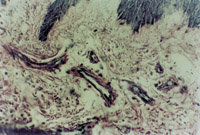

入院后立即用MEBO外涂保護(hù)創(chuàng)面,并行耕耘減張?zhí)幚?。傷?8h部分創(chuàng)面開始液化,傷后4天創(chuàng)面壞死組織已全部開始液化(圖5-3-3)。每3~4h清除創(chuàng)面液化物一次并外涂MEBO。

5-3-3 傷后4天,創(chuàng)面在MEBO作用下進(jìn)入液化期,創(chuàng)面皮膚組織開始再生